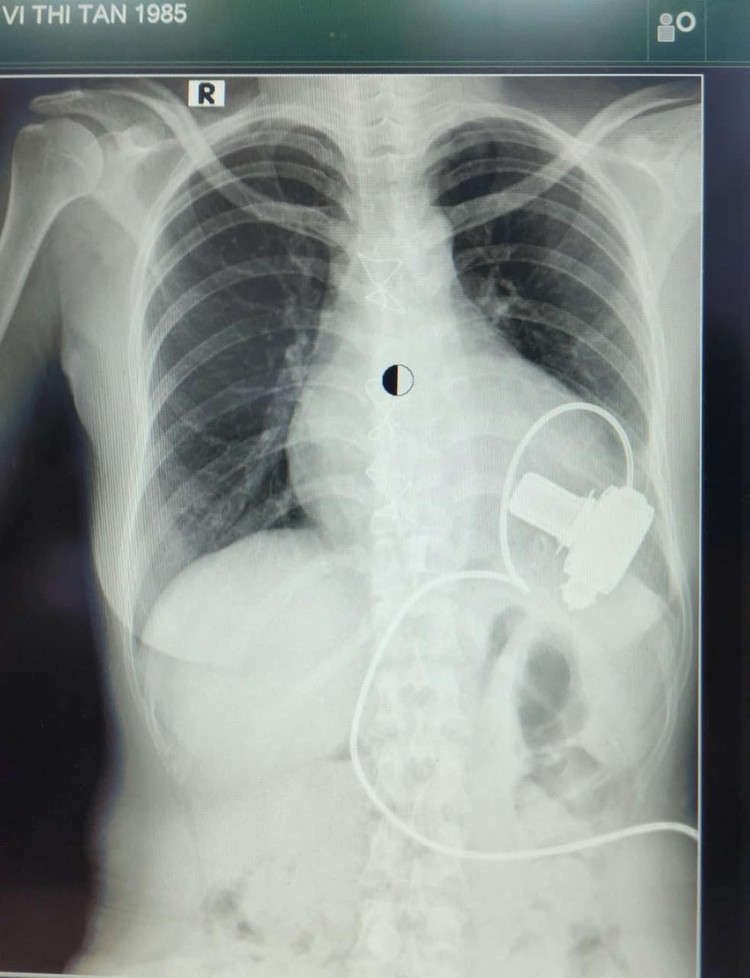

Cấy ghép tim nhân tạo hỗ trợ tâm thất LVAD là kỹ thuật mổ tim hở để cấy ghép một thiết bị bơm máu (hay gọi là tim cơ học) vào buồng tim trái với chức năng hút máu từ buồng tim trái rồi bơm máu vào động mạch chủ. LVAD sẽ hỗ trợ cho quả tim đã bị suy ở giai đoạn cuối không còn đáp ứng với các phương pháp điều trị nội khoa khác, đưa máu cung cấp oxi cho cơ thể, giúp tuần hoàn máu phục hồi.

| Cấy ghép tim nhân tạo hỗ trợ tâm thất LVAD ở bệnh nhân |